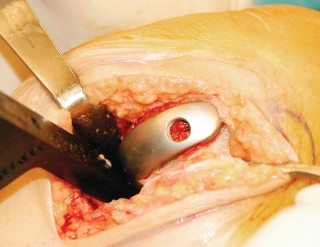

إجراء جراحة استبدال مفصل الركبة الجزئي (UKA)

تُعد جراحة استبدال مفصل الركبة الجزئي إجراءً دقيقًا يتطلب مهارة وخبرة عالية. يتبع الأستاذ الدكتور محمد هطيف في صنعاء بروتوكولات جراحية صارمة لضمان أفضل النتائج لمرضاه.

2. الوضع الجراحي والتعرض

- الوضع: يُوضع المريض في وضع الاستلقاء (Supine positioning) مع وضع كيس رمل أسفل الركبة أو حامل للساق يسمح بثني وفرد الركبة. يجب أن يكون الوضع مماثلاً لوضع جراحة TKA، مع استعداد لتحويل الإجراء إلى TKA إذا لزم الأمر.

- العاصبة (Tourniquet): تُستخدم عاصبة وتُوضع في أعلى الفخذ لتقليل النزيف.

-

الشق الجراحي:

يُستخدم شق طولي في الجانب الإنسي (الداخلي) من الركبة. يجب أن يكون الشق كبيرًا بما يكفي لتوفير رؤية جيدة للمفصل الرضفي الفخذي وإمكانية التحويل إلى TKA.

- فتح المفصل (Arthrotomy): يكون الفتح خطيًا وموازياً لألياف الوتر الرضفي، ويمتد إلى عظم الظنبوب وإلى الجزء السفلي من الرضفة.

- تحرير الأنسجة الرخوة: يتم قطع الغضروف الهلالي لتحرير الأنسجة الرخوة من عظم الظنبوب، ويتم تطوير سديلة تحت السمحاق في نمط دائري حول الظنبوب. يُمدد هذا التحرير خلفيًا لضمان توازن الأربطة.

-

تصحيح التشوه:

الهدف هو تحقيق تصحيح طفيف للتشوه، مع وجود رخاوة كاذبة طفيفة عند تطبيق ضغط تفحجي في نهاية الإجراء. يجب تجنب التصحيح المفرط.